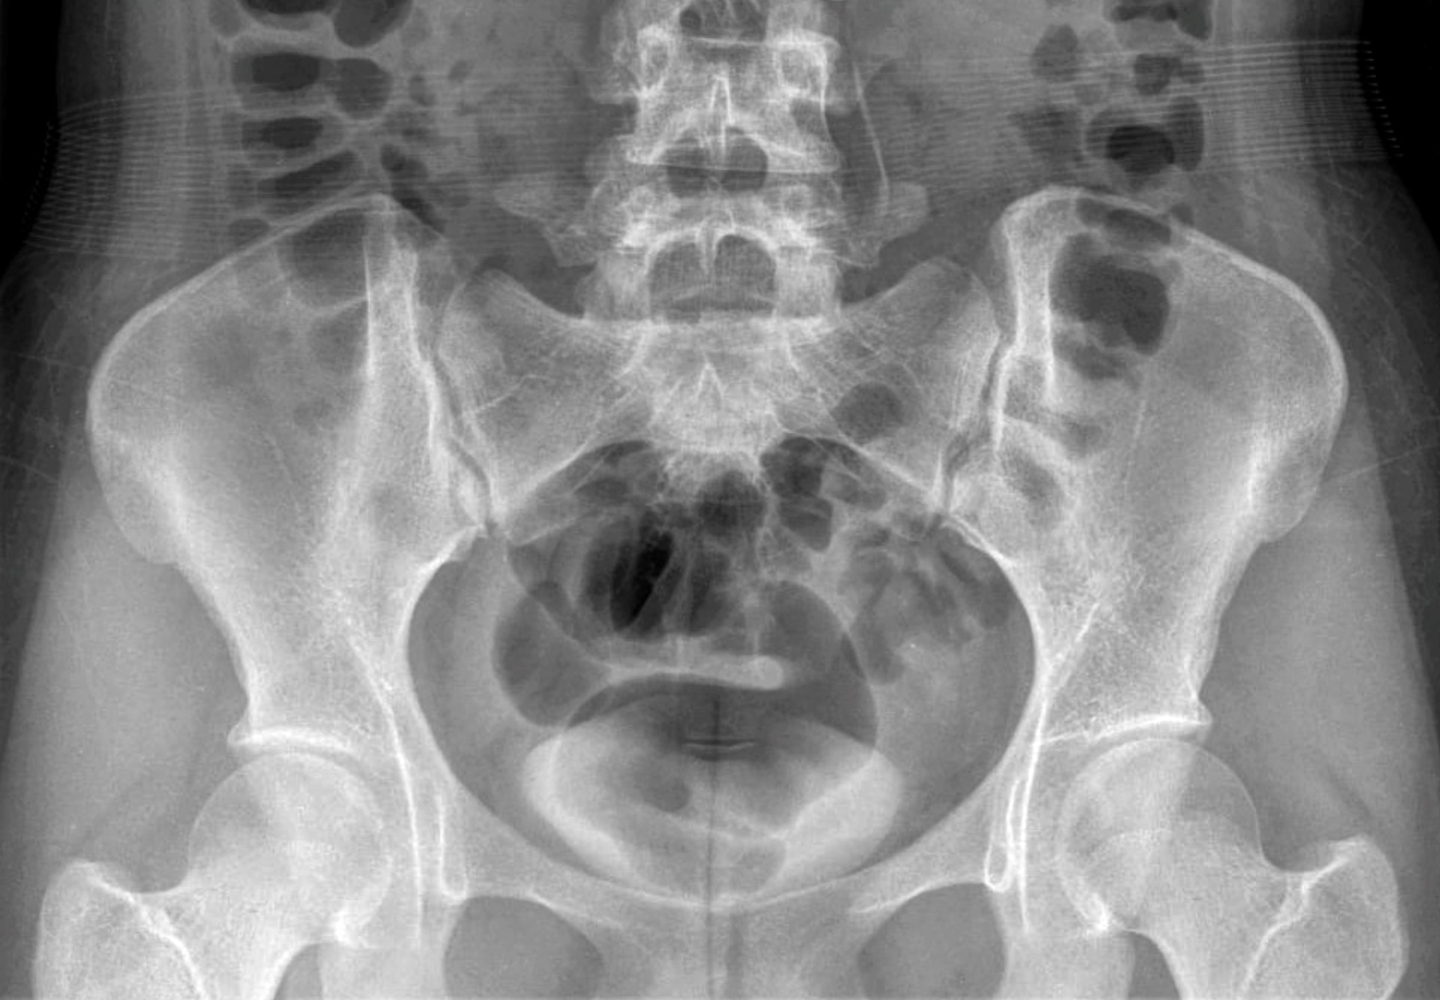

네, 특히 육안적 혈뇨가 보이거나 반복적으로 혈뇨가 나타나면 반드시 전문의 진료와 정밀검사를 받는 것이 중요합니다.

신장염, 요로감염, 신장결석, 방광암, 전립선비대증, 전립선암 등 다양한 질환이 원인이 될 수 있습니다.

증상이 없어 간과하기 쉽지만 원인 질환이 있을 수 있어 정기 검사가 중요합니다.

네, 젊은 층은 요로감염이나 결석이 많고 50대 이상은 방광암, 전립선 질환 등이 흔합니다.